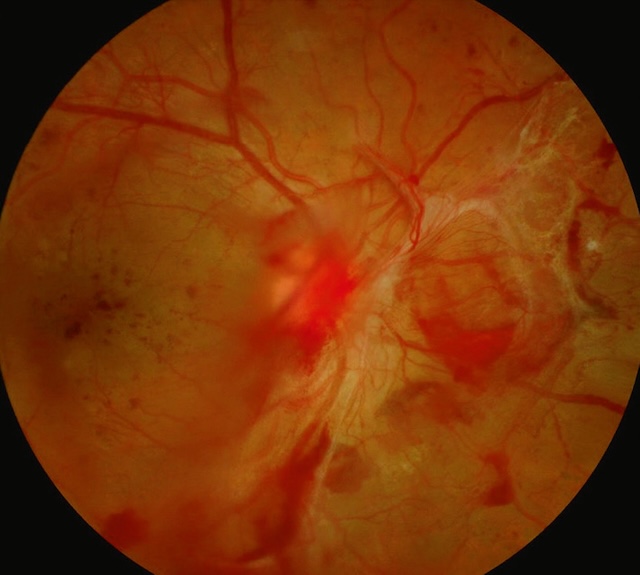

- – des hémorragies prérétiniennes ou intravitréennes surviennent à partir des néovaisseaux (fig. 20.9).

Fig. 20.9 Rétinopathie diabétique proliférante avec hémorragies prérétiniennes. L’image montre un fond d’œil typique d’une rétinopathie diabétique proliférante compliquée. Dans la partie inférieure, une large hémorragie prérétinienne s’étale en nappe, d’aspect sombre et dense, masquant partiellement les structures vasculaires sous-jacentes. On distingue en périphérie de fines tractions fibrovasculaires blanchâtres, traduisant l’organisation de néovaisseaux anciens. Les vaisseaux rétiniens sont tortueux, parfois dilatés, avec un fond d’œil diffusément altéré. Un discret œdème maculaire est aussi visible plus en arrière-plan. Ce tableau traduit une forme avancée de la pathologie, à risque élevé de complications comme un décollement tractionnel de la rétine.

Des complications peuvent survenir :

- • hémorragie intravitréenne par saignement des néovaisseaux prérétiniens ou prépapillaires;

- • décollement de la rétine dû à la traction exercée sur la rétine par le tissu fibreux de soutien des néovaisseaux (prolifération fibrovasculaire) : on parle de décollement de rétine par traction (fig. 20.10) par opposition au décollement de rétine rhegmatogène induit primitivement par une déchirure de la rétine;